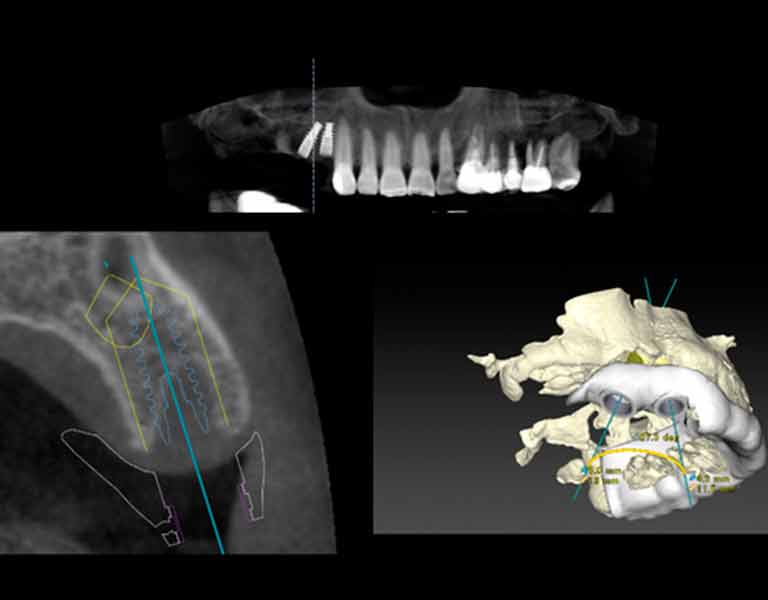

ノーベルガイドとは、CTで撮影した口腔内の画像からコンピューターの画面上で手術のシミュレーションをし、インプラントの埋入が正確に行われるように誘導するシステムです。

これにより、正確にインプラントを埋入できるだけでなく、従来よりも短い手術時間での埋入が可能になります。※状態によっては、ノーベルガイドが使用できない場合があります。

3D画像でインプラントの埋め入れ位置、角度を正確にシミュレーションします。CTスキャンデータから得られる詳細な情報を精査し、安全にインプラント治療が行えるように計画を立てます。